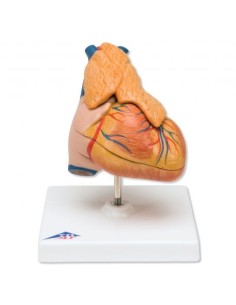

Dal cranio in 22 parti con incastri magnetici ai modelli di colonna vertebrale, da quelli di articolazioni a quelli di cuore, ogni pezzo della nostra collezione è progettato per un’immersione totale nello studio dell’anatomia umana. I nostri modelli, realizzati tramite scansioni di ossa vere, garantiscono un’esperienza tattile autentica e una fedeltà di peso quasi identica agli originali.